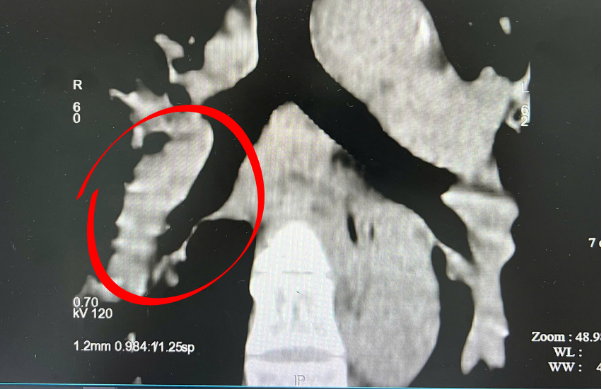

Ngay lập tức, chị P được chụp CT động mạch phổi để chẩn đoán xác định. Kết quả cho thấy bệnh nhân bị thuyên tắc động mạch phổi với mức nguy cơ trung bình cao - hoàn toàn trùng khớp với dự đoán ban đầu của bác sĩ.

Hình ảnh CT ghi nhận Thuyên tắc động mạch phổi